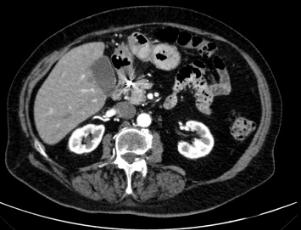

GE后,行静脉造影剂计算机断层扫描(CT)(图2)。CT扫描显示位于胃窦和幽门之间的外生和顶内肿块,在动脉期有明显的造影剂外渗。腹腔内未发现自由空气或腹腔积液的证据。诊断为大GAA。

图2、患者腹部CT,显示对比物明显外渗